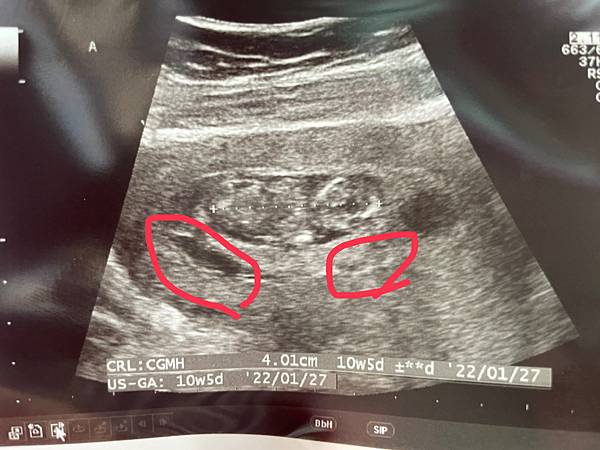

從第一次產檢到今天,中間又經歷過2次出血,真的一直讓人膽戰心驚...這天的回診,在手冊上被蓋了第二次的產檢章,所以就當今天是第二次產檢囉文章的描述就從第一次產檢後的每次的狀況講起...第一次剛產檢完沒幾天(7/5),就有在上廁所時擦到血,趕緊再打電話回去送子鳥,沒想到王醫生隔天有特別約診,所以他們幫我掛了王醫生的診看狀況,這真的是個驚喜,沒想到後面還有機會看到王醫生,看到他真的有種讓人放心的感覺❤️照超音波時,看到寶寶們還是很活潑的動來動去,也有乖乖長大,著實放心很多,不過在上面的寶寶旁邊有看到血塊,還好王醫生說應該不會影響寶寶,也順便問他對於羊穿跟NIPT的想法。王醫生的建議是做NIPT,避免風險狀況(大概我會一直出血,王醫生也怕不穩定吧?)。我也反問醫生:但上次一診那邊說NIPT雙胞胎準確度不好,只有8成,會不會有狀況沒檢測到?王醫生說其實不用太擔心,因為週數越大可以從母體抽到寶寶DNA的濃度就越高,相對也會越趨準確,讓我在12週左右抽血檢查其實就不用擔心太多。聽完真的放心不少,就決定先抽血檢查,後面再看是否要做羊穿,畢竟我也害怕羊穿的風險機率啊😂紅框就是有看到血塊的地方,原則上是肚子不要太用力應該就不會再一直出血才對